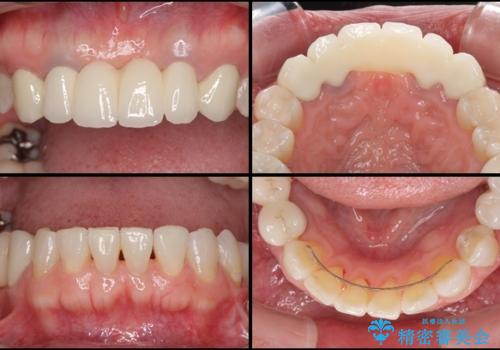

金属を使用した前歯のブリッジや奥歯の銀歯は全てオールセラミッククラウンまたはセラミックインレーとし、左下の奥歯はインプラントにより治療を行うこととしました。

遠方からの来院であったので、1回の治療時間を長めにし、できる限りの処置を集中して行うことで、来院回数を減らすことができました。

矯正治療までは考えていなかったそうですが、物が挟まっていた前歯のスペースがなくなり、矯正治療を行って良かったとのことでした。

初診カウンセリングを含めて13回の通院で治療を終えることができ、患者様には大変満足していただきました。